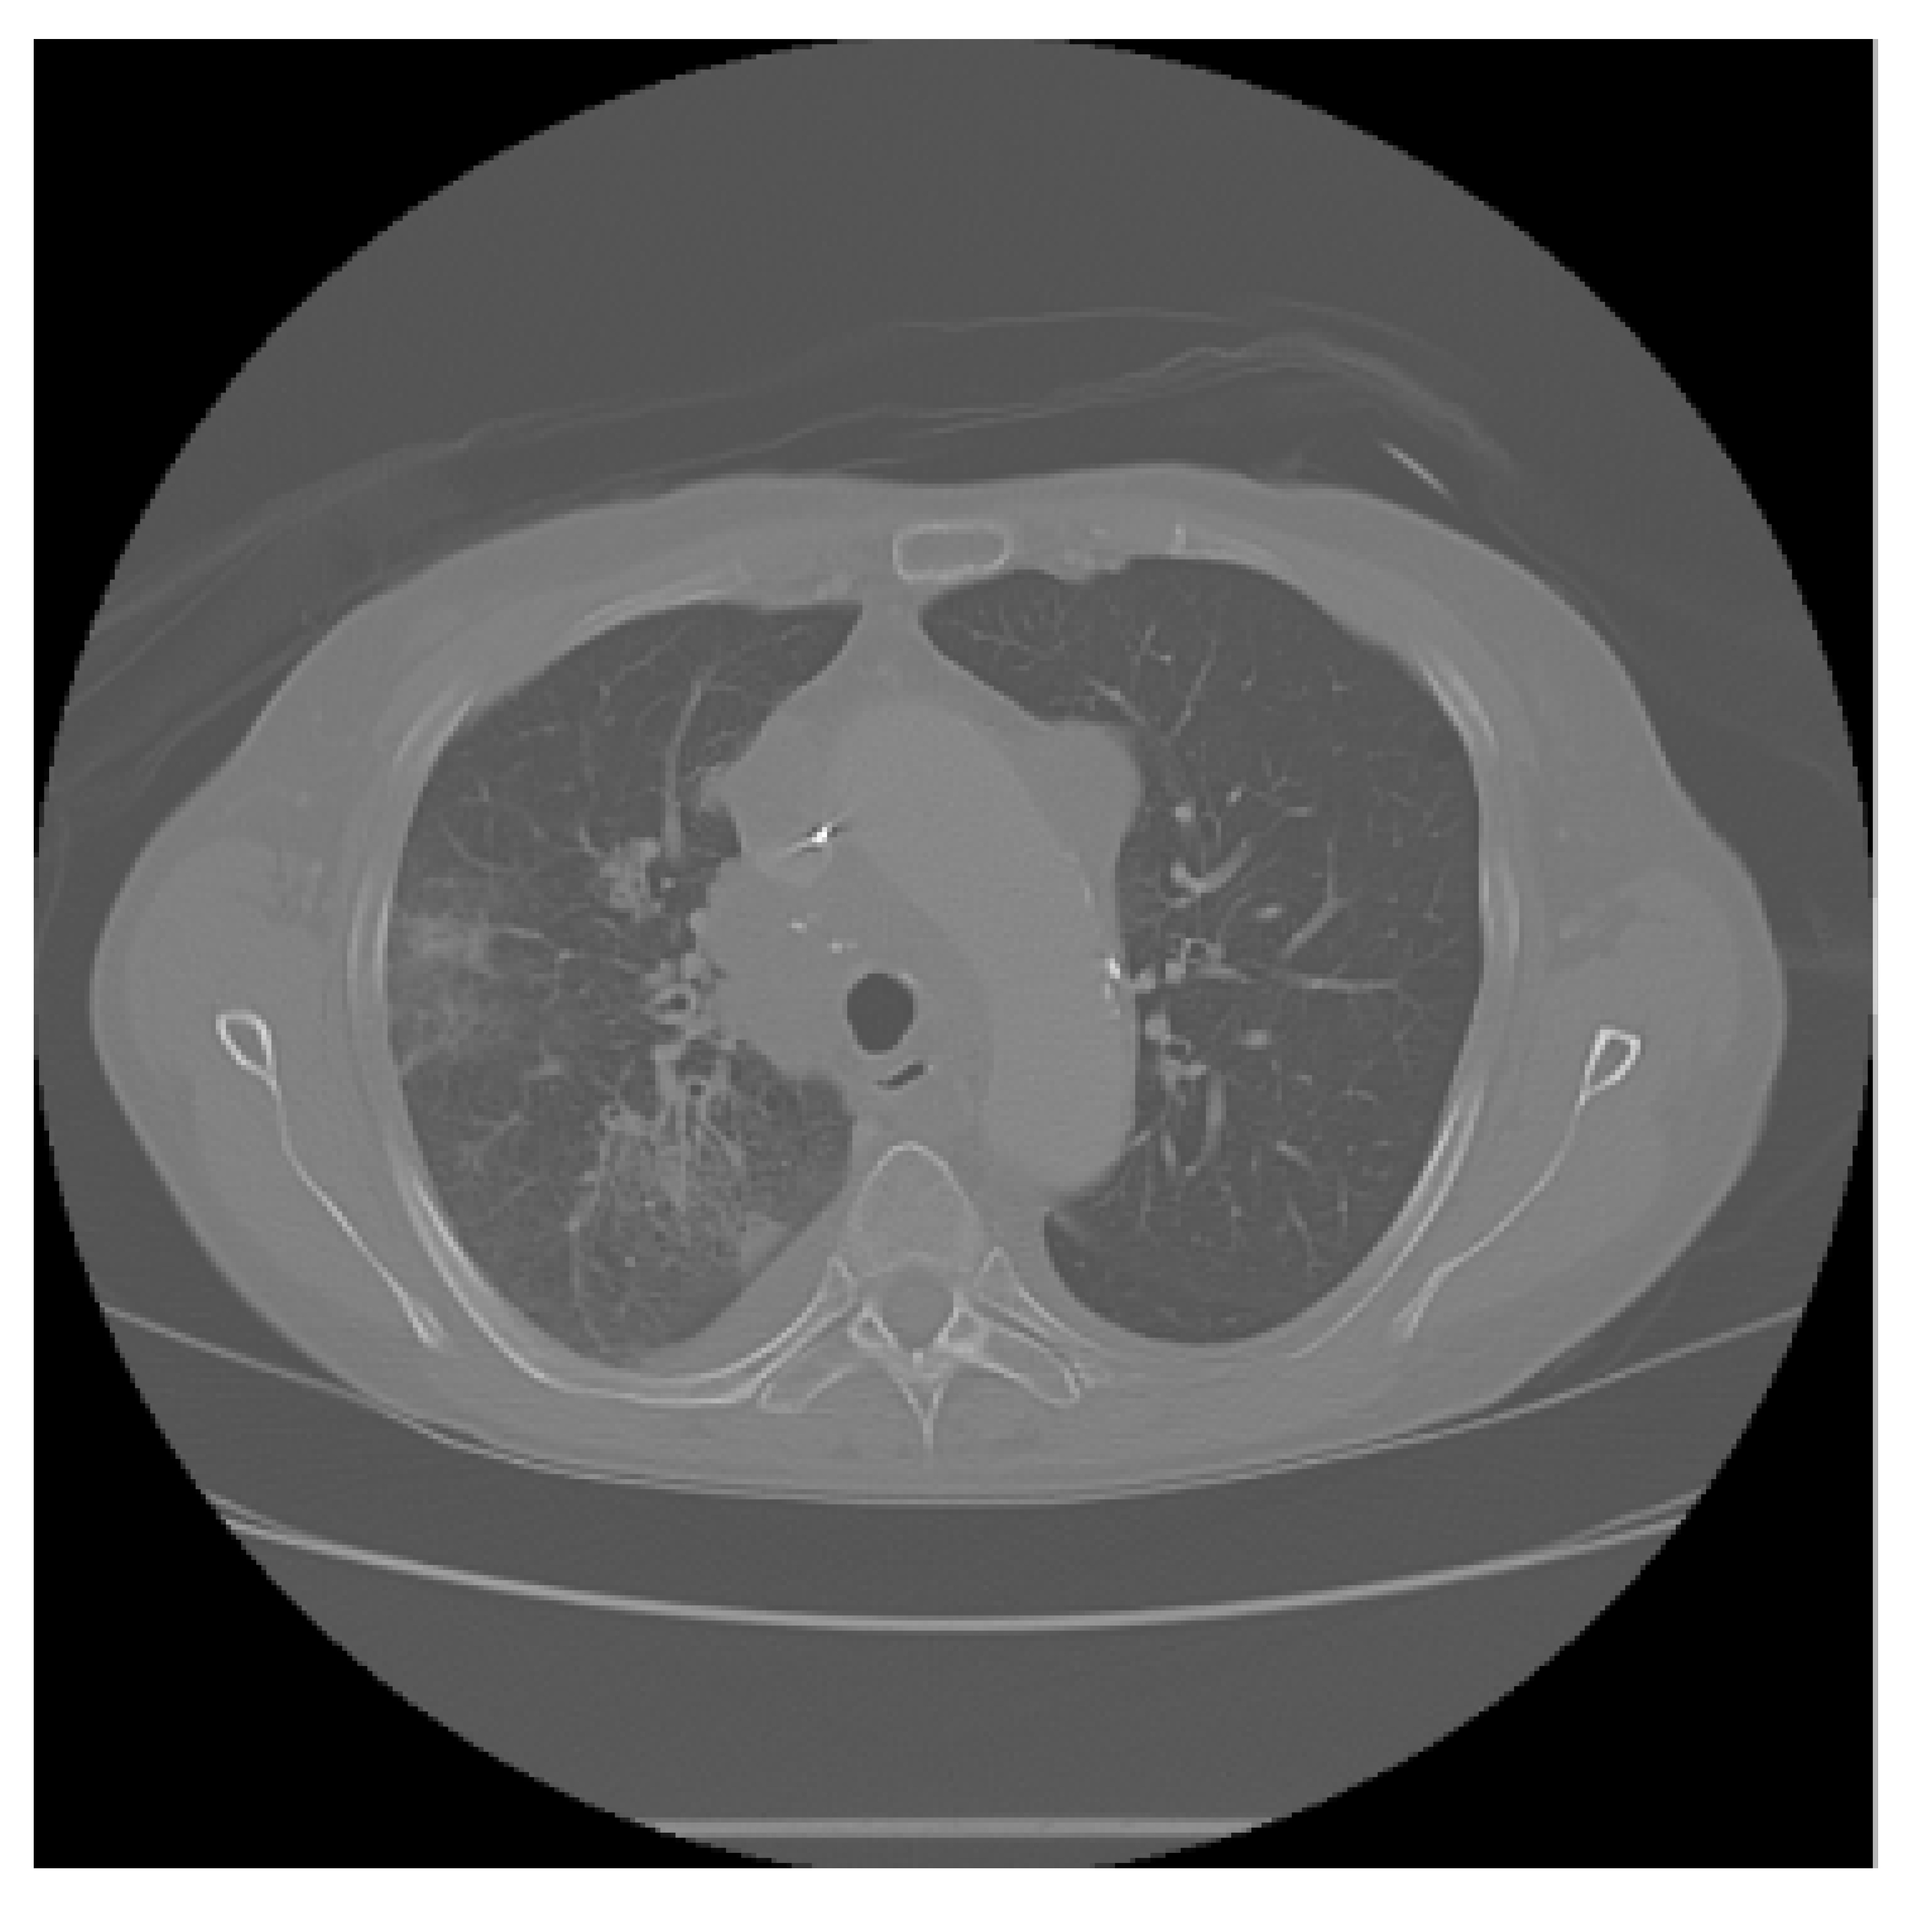

The APILungCancer interface provides intuitive functionality for loading and analyzing DICOM medical images. In the Load DICOM Images section, users can select and process CT scans for lung cancer evaluation. Once an image is loaded and analysis is performed, the software presents a visualization of the image along with the predicted probability of cancer (Table 7). Our study focused on lung cancer, including subtypes such as adenocarcinoma, squamous cell carcinoma, and small cell carcinoma. About 1000 training images and 300 test images from the CMB-LCA dataset were used to develop and validate the system.

In this example (Figure 5), the DICOM image 1-27.dcm from the test set was processed and the software calculated a cancer probability of 0.4267 (42.67%), indicating a high likelihood of malignancy.

Figure 5.

Determination of the probability of lung cancer. Example output of the system for the image 1-27.dcm, yielding a predicted probability of 42.67%, consistent with Table 7.

This value matches the result in Table 7, confirming the consistency of the predictions generated by the AI-based model integrated into the system.